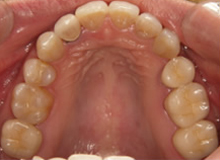

(治療後:写真右)

矯正治療をおこない歯列を整え、金属の詰め物はセラミッククラウンに換えて咬み合わせを再構成しました。

三本の小臼歯を抜歯していますが、歯並びを小さくしないようにしています。